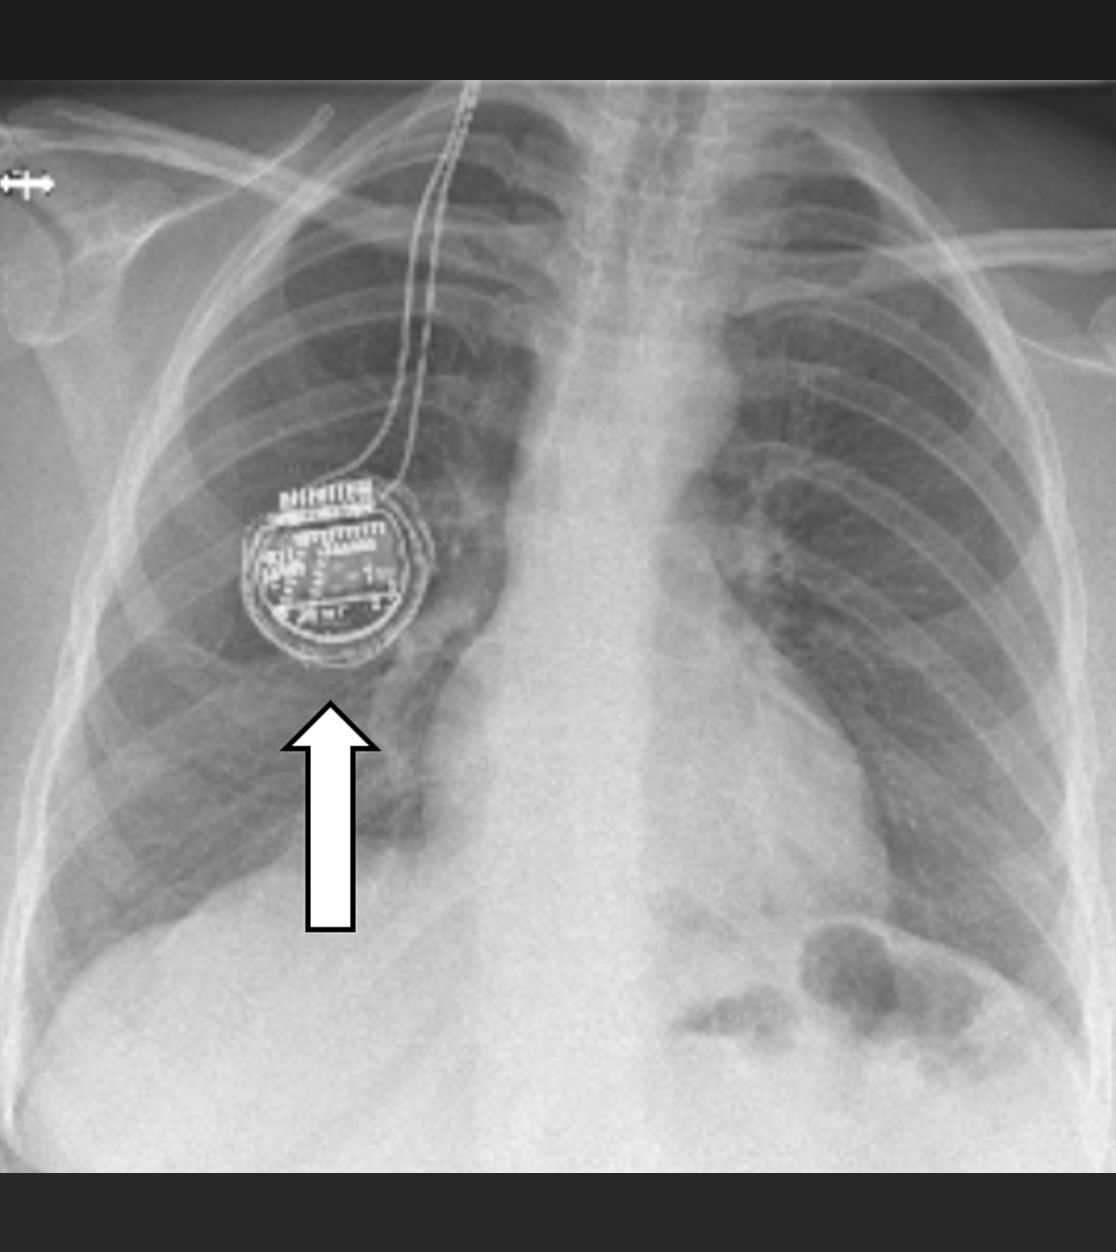

Bei der Rückenmarkstimulation wird in der Wirbelsäule eine Elektrode platziert. Über diese werden elektrische Impulse an das Rückenmark abgegeben. Die Elektrode ist mit einem Impulsgeber (vergleichbar mit einem Herzschrittmacher) verbunden. Das operative Verfahren gliedert sich in zwei Abschnitte: Im ersten Eingriff erfolgt, unter örtlicher Betäubung und Röntgenkontrolle, die Platzierung der Elektrode im Rückenmarkskanal. Im Anschluss erfolgt eine Testphase. Ziel ist es, die Abdeckung des Schmerzareals durch die Stimulation und die daraus resultierende Schmerzreduktion zu testen. Bei zufriedenstellendem Ergebnis wird in einem zweiten Eingriff der Impulsgeber unter die Haut implantiert.

Die über die Elektrode abgegebenen Impulse bewirken im Bereich des Rückenmarks eine Unterbrechung/Verminderung der Schmerzleitung der Nerven. Hierbei ist es notwendig, bei jedem Patienten individuell die notwendigen Stimulationsparameter festzulegen. Die schmerzreduzierende Wirkung der Neurostimulation kann in einem zweiten Schritt die Verringerung der Schmerzmedikation nach sich ziehen.

Röntgenbild zur Rückenmarkstimulation